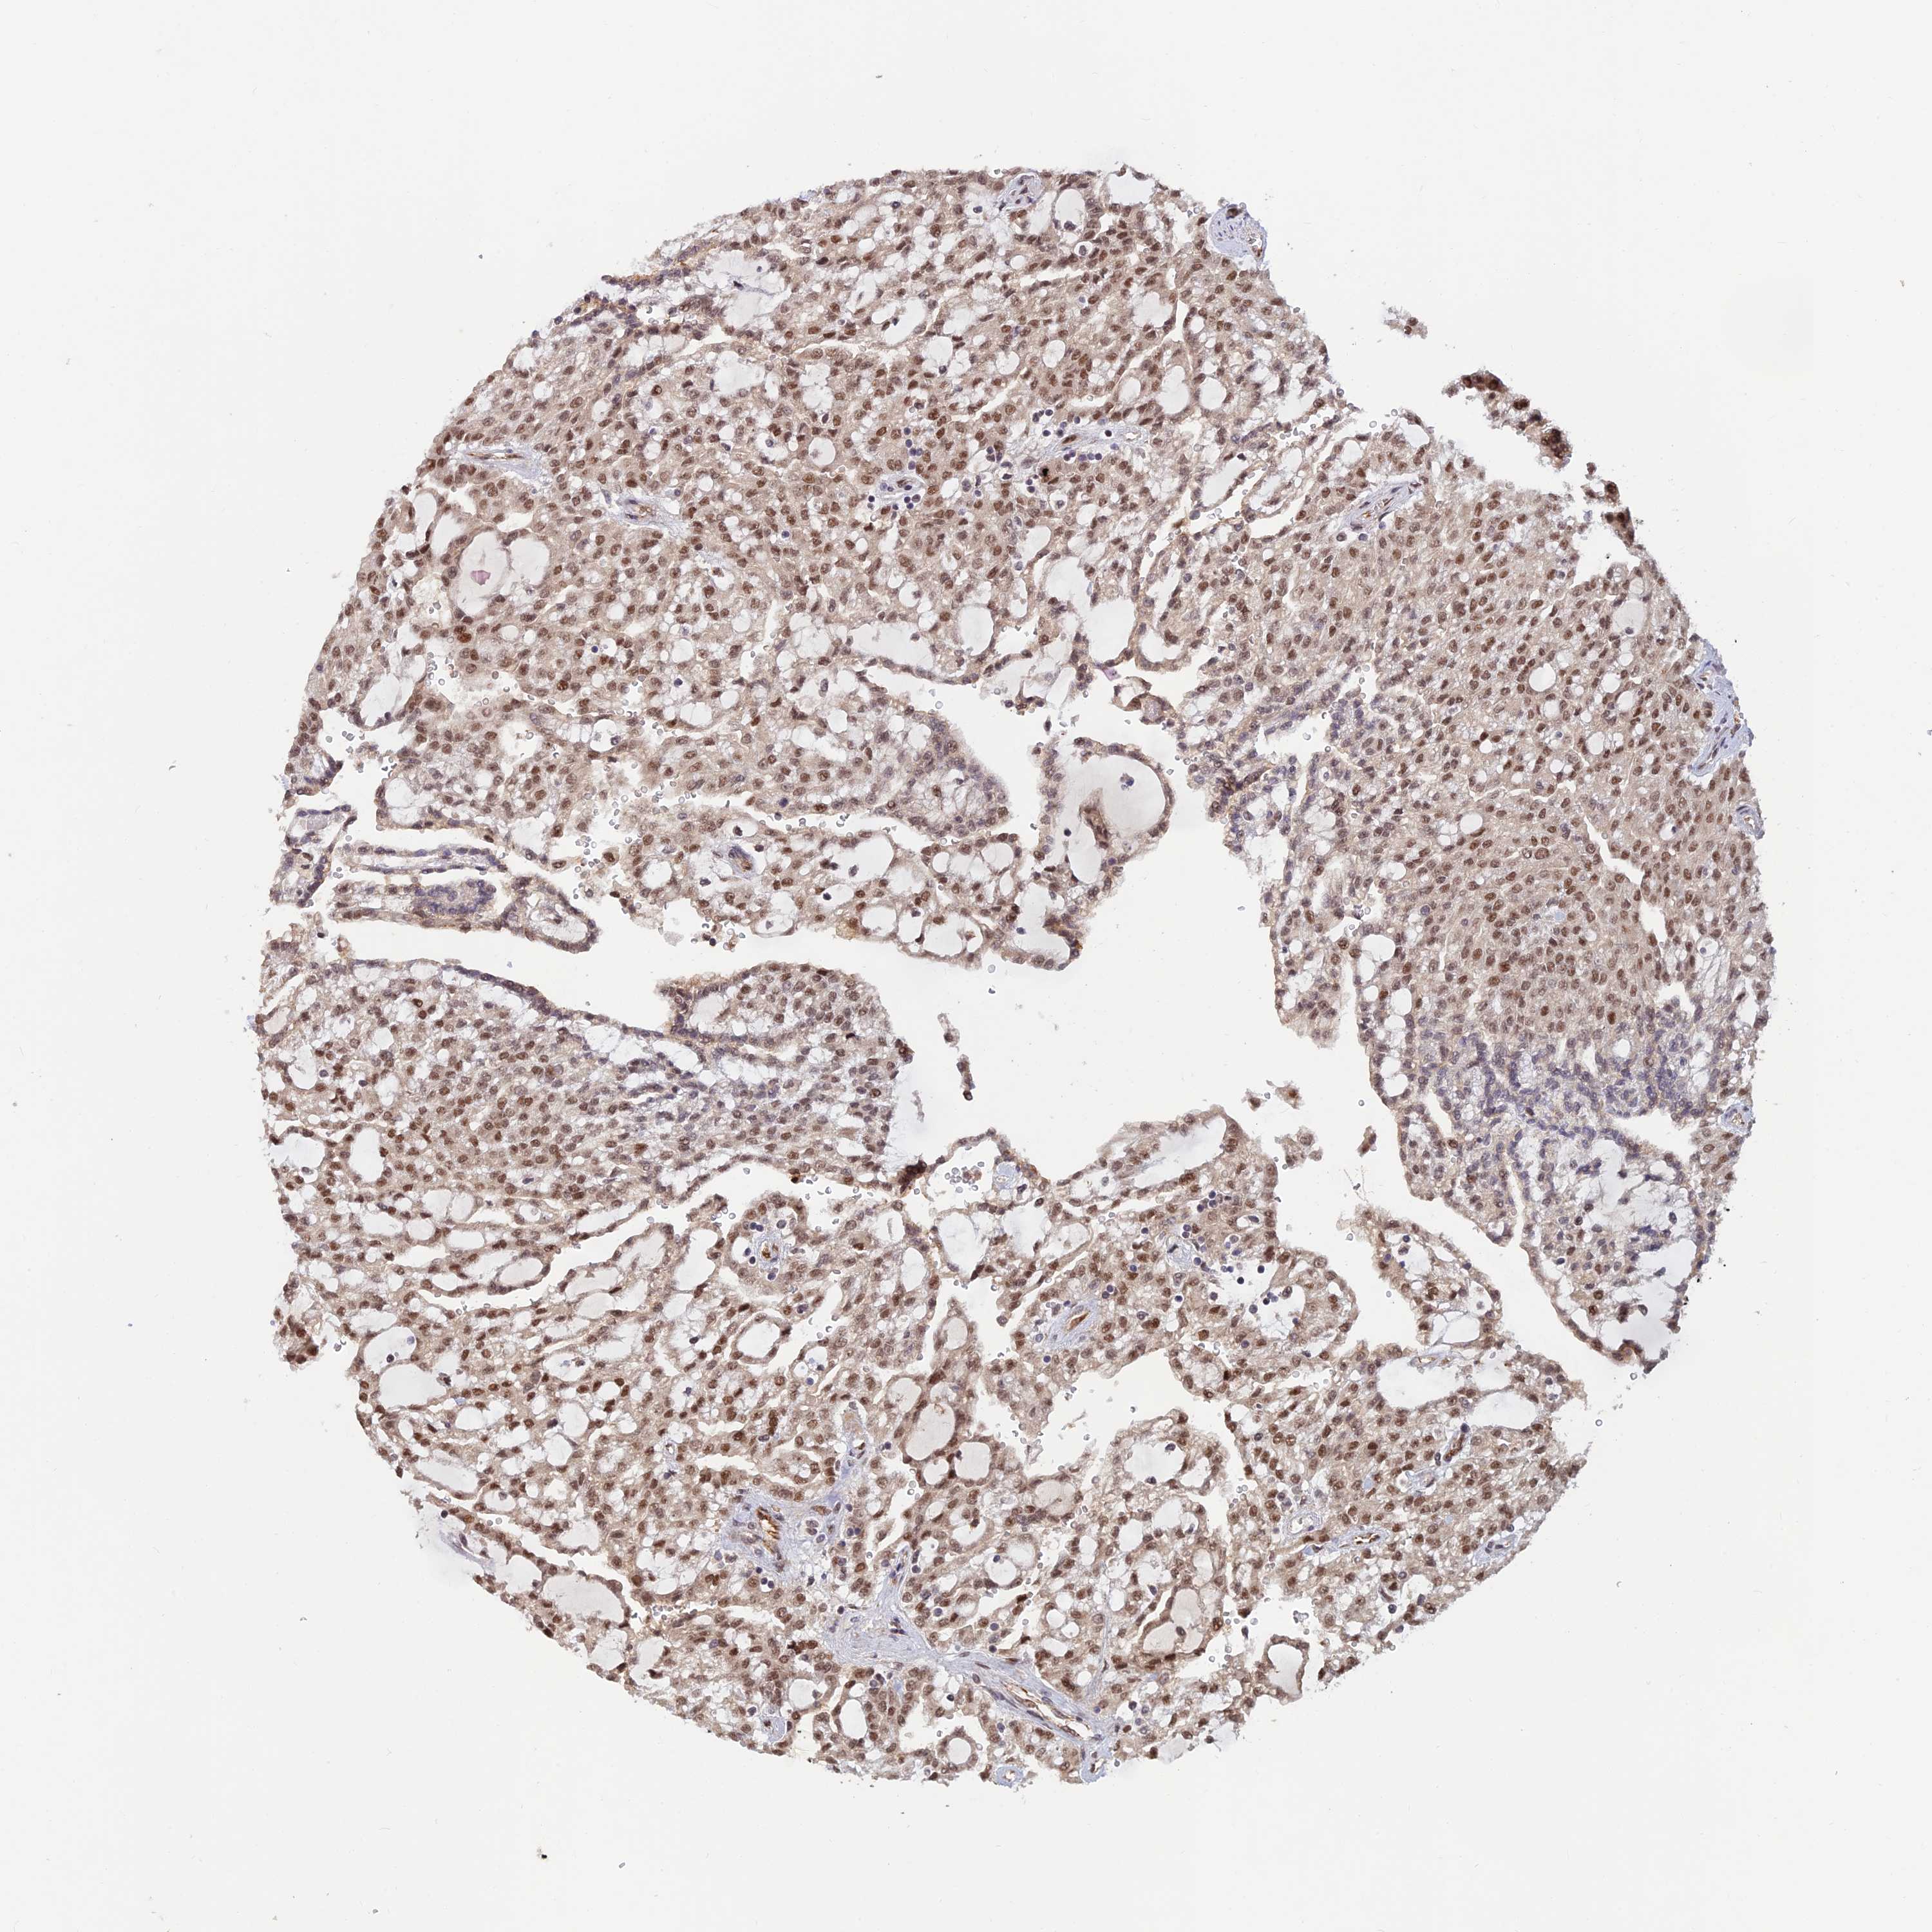

KIDNEY RENAL CLEAR CELL CARCINOMA (TCGA) - Interactive survival scatter ploti

The Survival Scatter plot shows the clinical status (i.e. dead or alive) for all individuals in the patient cohort, based on the same data that underlies the corresponding Kaplan-Meier plots. Patients that are alive at last time for follow-up are shown in blue and patients who have died during the study are shown in red.

The x-axis shows the expression levels (FPKM) of the investigated gene in the tumor tissue at the time of diagnosis. The y-axis shows the follow-up time after diagnosis (years). Both axes are complimented with kernel density curves demonstrating the data density over the axes. The top density plot shows the expression levels (FPKM) distribution among dead (red) and alive patients (blue). The right density plot shows the data density of the survived years of dead patients with high and low expression levels respectively, stratified using the cutoff indicated by the vertical dashed line through the Survival Scatter plot. This cutoff is automatically defined based on the FPKM cutoff that minimizes the p-score. The cutoff can be changed by dragging the vertical line or by entering a cutoff value in the square labeled "Current cut-off".

Under the Survival Scatter plot the p-score landscape (black curve; left axis) is shown together with dead median separation (red curve; right axis). Dead median separation is the difference in median mRNA expression between patients who have died with high and low expression, respectively. It is calculated as follows: median FPKM expression of dead patients with high expression - median FPKM expression of dead patients with low expression. This is intended to aid the user in visually exploring custom cutoffs and the associated p-scores and dead median separation.

Individual patient data is displayed and can be filtered by clicking on one or more of the category buttons on the top of the page. Categories describing expression level and patient information include: high, low, alive, dead, female, male and tumor stages. The scale of the x-axis can be toggled between linear and log-scale by clicking on the "x log" button. Mouse-over function shows TCGA ID, patient information and mRNA expression (FPKM) for each patient.

& Survival analysisi

Kaplan-Meier plots summarize results from analysis of correlation between mRNA expression level and patient survival. Patients were divided based on level of expression into one of the two groups "low" (under cut off) or "high" (over cut off). X-axis shows time for survival (years) and y-axis shows the probability of survival, where 1.0 corresponds to 100 percent.

ZNF565 is not prognostic in Kidney Renal Clear Cell Carcinoma (TCGA)

Best expression cut offi

Based on the FPKM value of each gene, patients were classified into two groups and association between prognosis (survival) and gene expression (FPKM) was examined. The best expression cut-off refers the FPKM value that yields maximal difference with regard to survival between the two groups at the lowest log-rank P-value. Best expression cut-off was selected based on survival analysis .

When clicking on this number, the vertical dashed line indicating cut-off, the interactive survival plot, and the Kaplan-Meier curve will be adjusted to show results based on the best expression cut-off.

: 2.7

Median expressioni

Median expression refers to the median FPKM value calculated based on the gene expression (FPKM) data from all patients in this dataset. When clicking on this number, the vertical dashed line indicating cut-off, the interactive survival plot, and the Kaplan-Meier curve will be adjusted to show results based on the median expression.

: N/A

P scorei

Log-rank P value for Kaplan-Meier plot showing results from analysis of correlation between mRNA expression level and patient survival.

N/A

5-year survival highi

5-year survival for patients with higher expression than the expression cutoff.

For melanoma and glioma, 3-year survival is shown.

5-year survival lowi

5-year survival for patients with lower expression than the expression cutoff.

TCGA RNA samplesi

RNA-seq data is reported as average FPKM (number Fragments Per Kilobase of exon per Million reads), generated by the The Cancer Genome Atlas (TCGA) .

Normal distribution across the dataset is visualized with box plots, shown as median and 25th and 75th percentiles. Points are displayed as outliers if they are above or below 1.5 times the interquartile range. FPKM values of the individual samples are presented next to the box plot.

Average pTPM 2.6

Number of samples 521